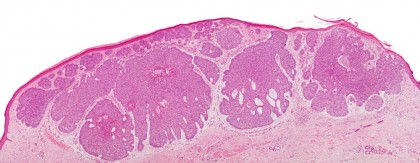

Diagnosticul este in primul rand clinic, dar trebuie sustinut prin examenul histopatologic al unui fragment din leziunea suspecta (sau al intregii leziuni daca are dimensiuni mici). Daca exista limfadenopatie se indica biopsia prin ac fin sau excizie urmata de examenul histoatologic.Examen histologic

Carcinomul spinocelular in situ se caracterizeaza prin keratinocite atipice intraepidermice cu proliferare. Se observa in epiderm hiperkeratoza, acantoza, parakeratoza confluenta. Keratinocitele au aspect clasic dezordonat ca fiind suflate de vint. Atipia celulara, nucleii hipercromatici si mitozele sunt predominante. Keratinocitele atipice pot fi gasite in stratul bazal si se extind pina la foliculii de par, dar nu invadeaza dermul.Caracteristica principala care diferentiaza carcinomul invaziv de cel in situ este invazia keratinocitelor maligne prin membrane bazala in derm. Variantele de carcinom spinocelular cuprind: keratoacantomul, carcinomul acantolitic, carcinomul verucos si carcinomul sarcomatoid.